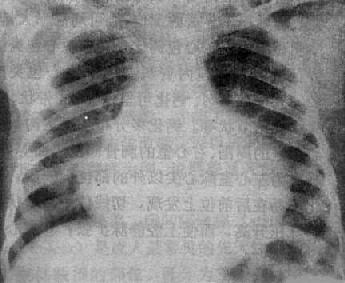

X线表现 (图3-2-18),不论积液的性质和病原如何,都可以显示其共同特点:①心包积液在300ml以下者,心影大小和形状可无明显改变,X线难以发现。中等量积液,液体从心包囊最下部分向心两侧扩展,后前位可见心影向两侧普遍增大,心缘正常弧度消失,心形状呈烧瓶状,如积液缓慢增多,则呈球形;②心包积液可使体静脉血液回流至右心房受阻,致使上腔静脉增宽;③由于心包在心底部的附着处高于心与大血管的交界下,增大的心影可以超过心、大血管交界处,增大的心影可以超过心、大血管交界以上,故使主动脉影缩短;④心缘搏动减弱或消失,而主动脉搏动则表现正常;⑤体静脉血液回流到右心房受阻,右心室排血量减少,因而肺纹理减少或不显。如合并左心衰竭,则有肺瘀血现象。

图3-2-18 心包积液(后前位)

心影向两侧普遍增大,心缘正常弧度消失,

上腔静脉增宽,主动脉影缩短,肺纹理减少